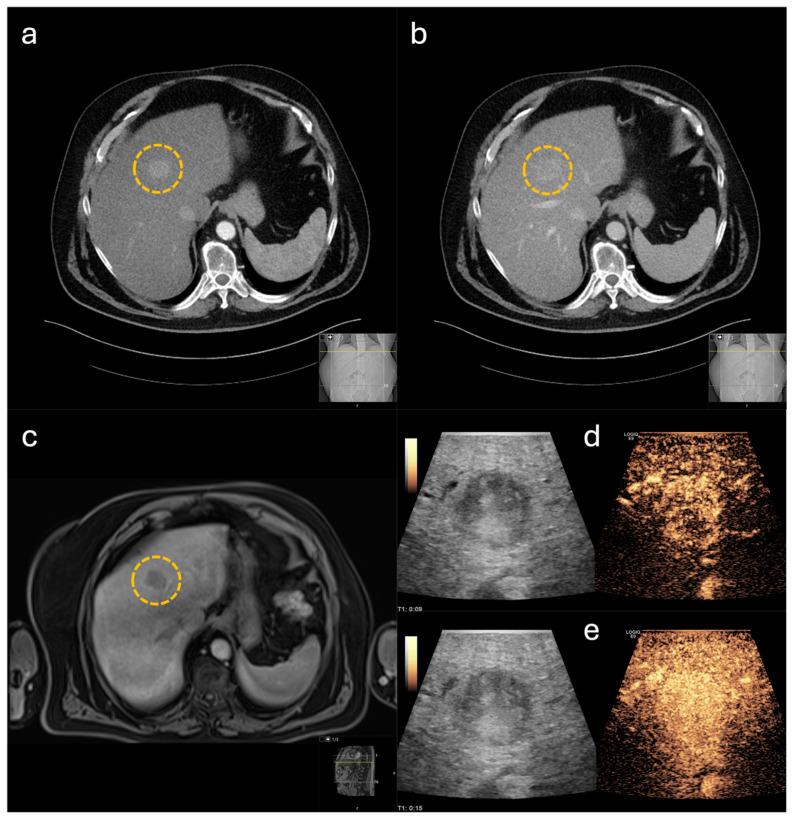

The aim of this study was to evaluate the performance and the impact of contrast-enhanced intraoperative ultrasound (CE-IOUS) on intraoperative decision-making, as there is still no standardized protocol for its use. Therefore, we retrospectively analyzed multiple CE-IOUS performed in hepato-pancreatic-biliary surgery with respect to pre- and postoperative imaging and histopathological findings.

Data of 50 patients who underwent hepato-pancreatic-biliary surgery between 03/2022 and 03/2024 were retrospectively collected. CE-IOUS was performed with a linear 6-9 MHz multifrequency probe connected to a high-resolution device. The ultrasound contrast agent used was a stabilized aqueous suspension of sulphur hexafluoride microbubbles.

In total, all 50 lesions indicated for surgery were correctly identified. In 30 cases, CE-IOUS was used to localize the primary lesion and to define the resection margins. In the remaining 20 cases, CE-IOUS identified an additional lesion. Fifteen of these findings were identified as malignant. In eight of these cases, the additional malignant lesion was subsequently resected. In the remaining seven cases, CE-IOUS again revealed an inoperable situation. In summary, CE-IOUS diagnostics resulted in a high correct classification rate of 95.7%, with positive and negative predictive values of 95.2% and 100.0%, respectively.

CE-IOUS shows excellent performance in describing intraoperative findings in hepato-pancreatic-biliary surgery, leading to a substantial impact on intraoperative decision-making.